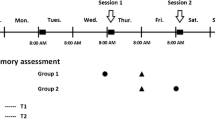

Spatial working memory task paradigm

As in our previous studies (Huang et al. 2016; Liao et al. 2012; Yin et al. 2012), the spatial working memory of all subjects was assessed using a block-designed n-back task with three load conditions (0-, 1-, and 2- back) during fMRI scanning (Fig. 1a). White box (white on a black background) was presented to participants in pseudorandom order. In 0-back task, all subjects needed to determine whether the current position of the white box is the same as that first presented, while in 1- and 2- back task, to determine whether the current position of the white box is the same as that presented in the previous one or two stimuli. Participants answered by pressing the response button (right button for “YES”, and left button for “NO”) with both hands thumb.

Spatial working memory task paradigm. (a) A blocked design n-back task with three task conditions (0-, 1-, and 2- back). (b) All subjects underwent four fMRI scans (Run-1 -2, −3, −4, with Run-3 the same as Run-1, and Run-4 the same as Run-2), each fMRI scan contained two epochs, each epoch comprised four blocks, 0-, 1-, 2- back condition task block, followed by a baseline control block

All the subjects underwent four fMRI scans (Run-1 -2, −3, −4, Run-3 was the same as Run-1, and Run-4 was the same as Run-2), each fMRI scan contained two epochs, each epoch comprised four blocks, three load conditions (0-, 1-, and 2- back) blocks, followed by a resting-state (“Rest”) block as baseline control (Fig. 1b). Each task block contained a 3 s task prompt and a 30 s task stimulus (10 stimuli, each displayed for 2 s and followed by a fixed crossover for 1 s). The “Rest” block lasted 33 s with the fixed crossover. Thus, each fMRI scan took 264 s.

Participants were well trained and practiced before the fMRI scan to ensure they understood the requirements of our task. The n-back task paradigm was presented using E-prime 2.0 software (https://pstnet.com/products/e-prime) on a computer that was compatible and synchronized with the MR device. The response accuracy and reaction times during task completion could be recorded simultaneously, along with recording the numbers of correct button presses in response to targets (= hits), the numbers of incorrect button presses in response to non-targets (= commission errors or false alarms), and the numbers of no button presses in response to targets (= omission errors or misses).